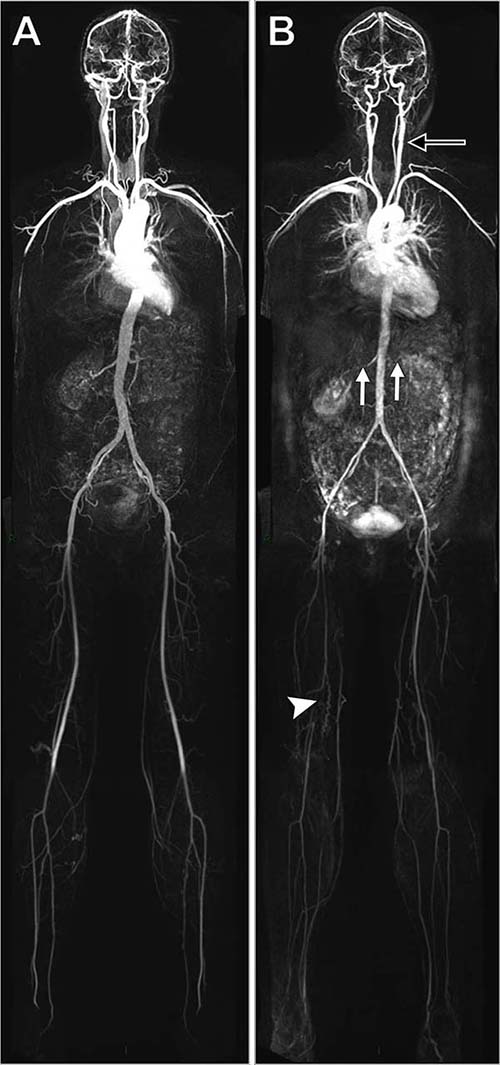

Whole-body MRA allows for detection of early atherosclerotic disease

Researchers using whole-body magnetic resonance angiography (MRA) have found a surprisingly high prevalence of atherosclerosis in people considered to be at low to intermediate risk for cardiovascular disease, according to a new study in Radiology.

Whole body MRA was used to quantify the burden and distribution of asymptomatic atherosclerosis in 1,513 people, average age 53.5 years old, who had a 10-year cardiovascular disease risk of less than 20 percent. Almost half of the participants (49.4 percent) had at least one vessel with stenotic disease and more than a quarter (27 percent) had multiple stenotic vessels.

Researchers assessed 31 arterial segments in each participants including left and right carotid, vertebral, subclavian and renal arteries. Each arterial segment was visually assessed for the region of greatest stenosis and was coded according to the maximum stenosis present within the vessel and the presence of aneurysmal dilation. The vast majority of arterial segments (94.7 percent) were assessed as normal.